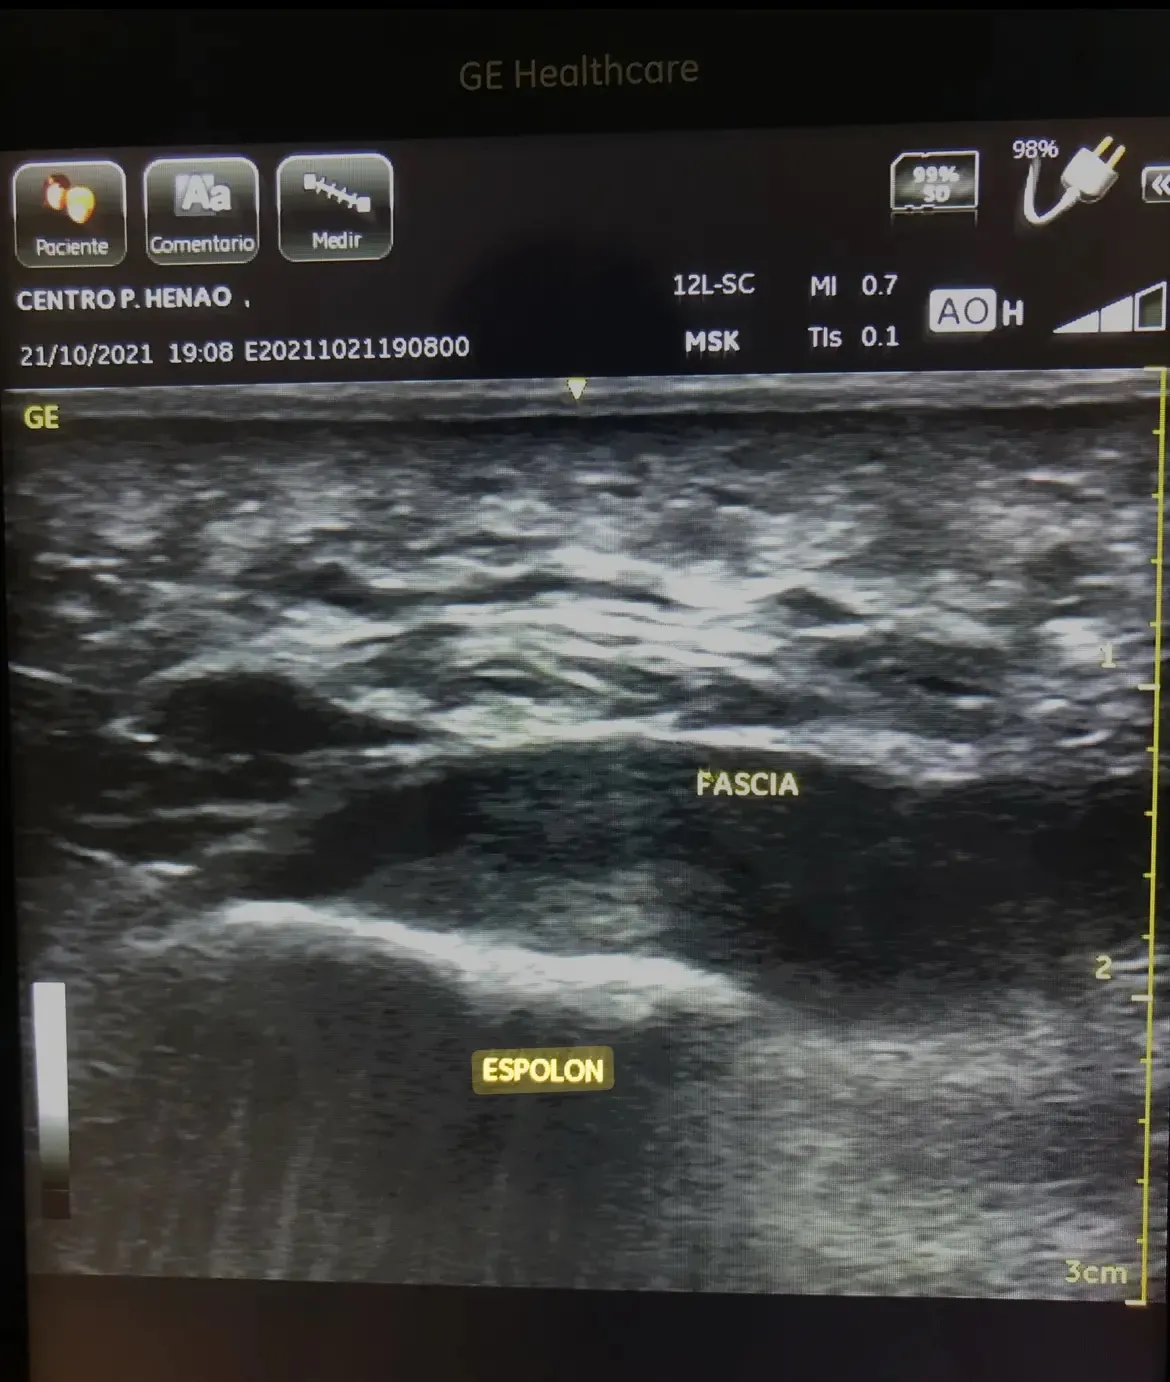

La Ecografía: La Imagen que lo Cambia Todo

Las radiografías son una excelente herramienta para valorar hueso, pero no se ven los tejidos blandos de alrededor. Por eso utilizamos la ecografía podológica como herramienta diagnóstica fundamental.

Al colocar el transductor ecográfico sobre el talón de Roberto, la imagen fue clara e inequívoca:

- Fascia plantar engrosada: 6,5 mm (lo normal es menos de 4 mm)

- Hipoecogenicidad marcada: indicativo de inflamación crónica y degeneración del tejido

- Pérdida del patrón fibrilar normal: señal de lesión

- Espolón calcáneo visible: como un hallazgo más, sin signos inflamatorios asociados

“¿Ve esto, Roberto? Esta zona oscura y engrosada es su fascia plantar inflamada. El espolón está ahí, sí, pero es un espectador inocente”.

En la ecografía de control, la fascia plantar mostraba una mejoría notable: reducción del grosor a 4,8 mm y recuperación parcial del patrón fibrilar normal.